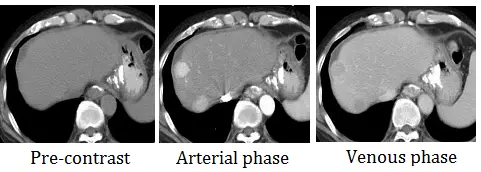

本題提供了三張肝臟電腦斷層影像,分別為:

- Pre-contrast (無對比劑/平掃相):在肝臟右葉可見一邊界較為模糊、相對於正常肝實質呈現略低密度 (hypodense) 的結節狀病灶。

- Arterial phase (動脈相):注射對比劑後,此時主動脈 (Aorta) 呈現極高密度。原本低密度的肝臟病灶呈現強烈且均勻的顯影 (hyperdense),亮度明顯高於周圍尚未完全顯影的正常肝臟實質,此現象稱為「對比劑早期流入 (Wash-in)」,代表該病灶具有豐富的動脈血流供應。

- Venous phase (靜脈相/門靜脈相):主動脈密度下降,肝靜脈與門靜脈分支顯影。此時原本強烈顯影的病灶,其密度迅速下降,甚至低於周圍已充分顯影的正常肝臟實質,呈現相對低密度 (hypodense),此現象稱為「對比劑排空 (Wash-out)」。

綜合以上特徵:「**動脈相